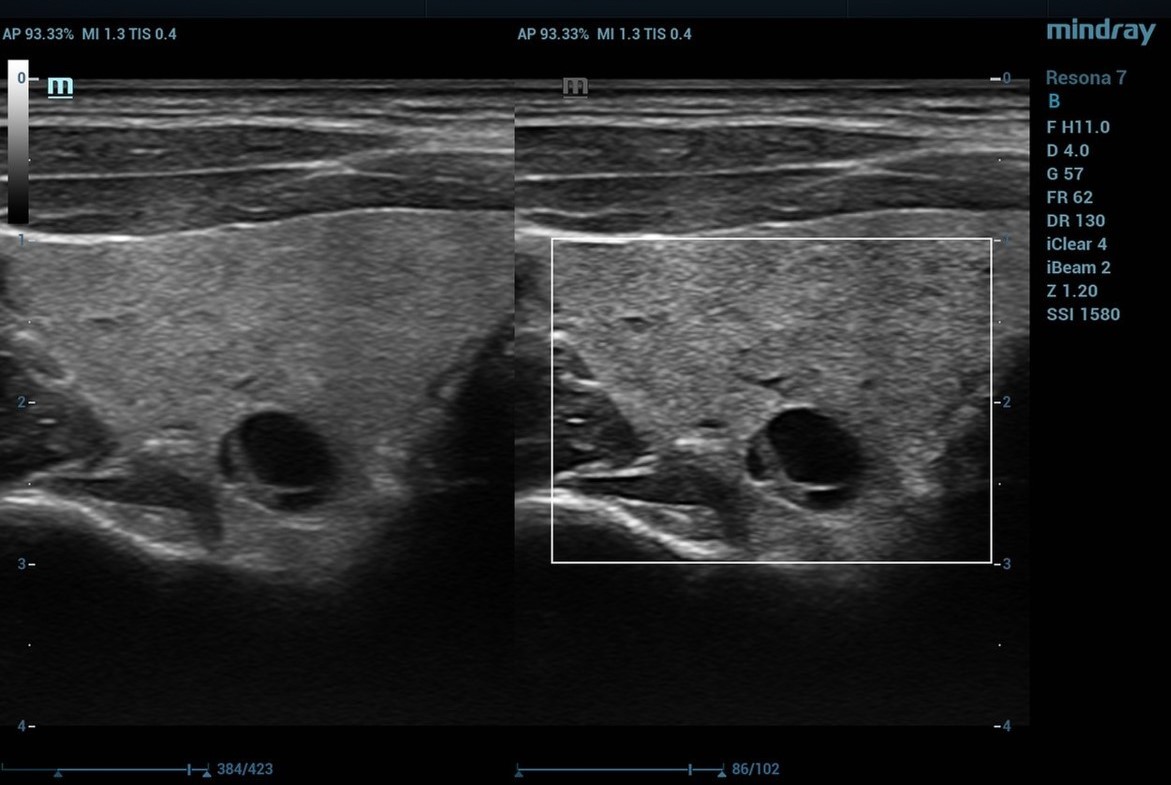

Advanced Acoustic Acquisition (AAA) is a software-based data acquisition method that captures up to 90% of the returning acoustic data and then processes it up to 10x faster by interrogating a relatively smaller number of large zones and extracting more information from each acquisition. Conventional ultrasound systems can capture only a few receive data sets from each transmit event due to processing time requirements for each data set which creates an acoustic acquisition backlog that results in processing constraints. This inherent limitation is overcome by using a flexible, software-based channel domain processor.

produce high quality images, the region of interest must be sufficiently sampled in both the axial and lateral dimensions to prevent several types of imaging artifacts. Dynamic Pixel Focusing permits utilization of the complete channel data set received from multiple, overlapping zones to retrospectively improve the position and focus of each individual data point. Using software algorithms to synthetically focus along every point in the receive beam effectively produces a round-trip beam focused at all depths, eliminating the need for multiple transmit foci. The image is 2-way focused at every point. A typical ZST+ ultrasound image has over 500 range samples, so the net effect is equivalent to a conventional beamformer-based system using 500-600 focal zones.